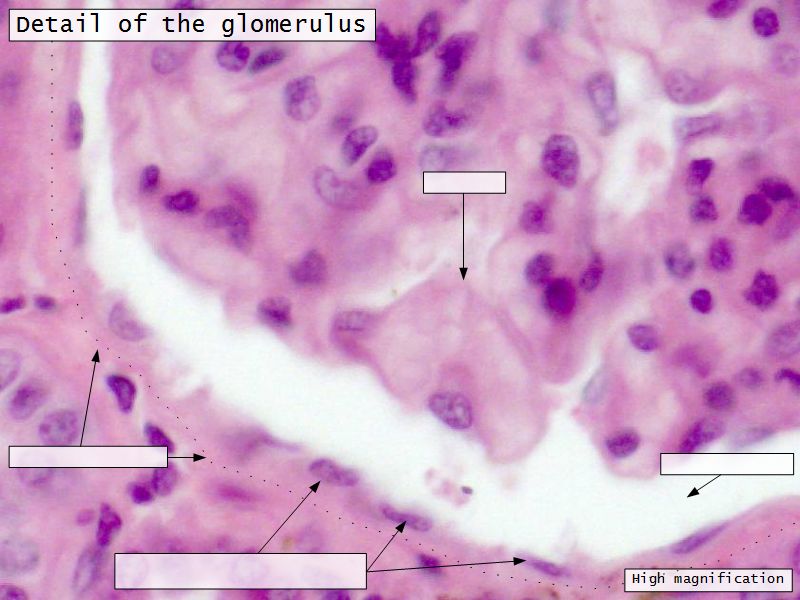

Epithelium layers

- Capillary endothelium

- Visceral layer of epithelium

- Podocytes

- Resting on glomerular basement membrane

- Capsular space

- Parietal layer of epithelium

- Simple squamous epithelium

Glomerular filtration barrier

- Three layers

- Fenestrated epithelium

- Exclude blood cells & platelets

- Glomerular basement membrane

- Main filtration barrier

- Thick

- Fused epithelial & endothelial BM

- Replenished by podocytes due to removal by mesangial cells

- Glomerular epithelium

- Through filtration slit

Podocytes

- Visceral layer of epithelium

- Protrude into capsular space

- Attached to basement membrane

- Long cytoplasmic extensions

- Primary processes

- Secondary processes

- Podocyte feet

- Tightly spaced

- Filtration slits 20 - 30 nm wide